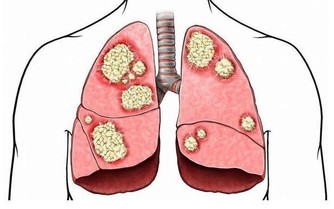

***2、呼吸不暢,胸悶心慌***

體內長期缺鉀會導致人們的呼吸產生異常,因為心臟供血的能力受到心肌失常的影響,會導致人體出現胸悶心慌的症狀,特別是存在高血壓等疾病的人群,症狀會更明顯。如果覺得呼吸不暢心慌胸悶的症狀出現的更加頻繁,應該及早檢查一下人體內是否缺鉀,並且及時的補充。